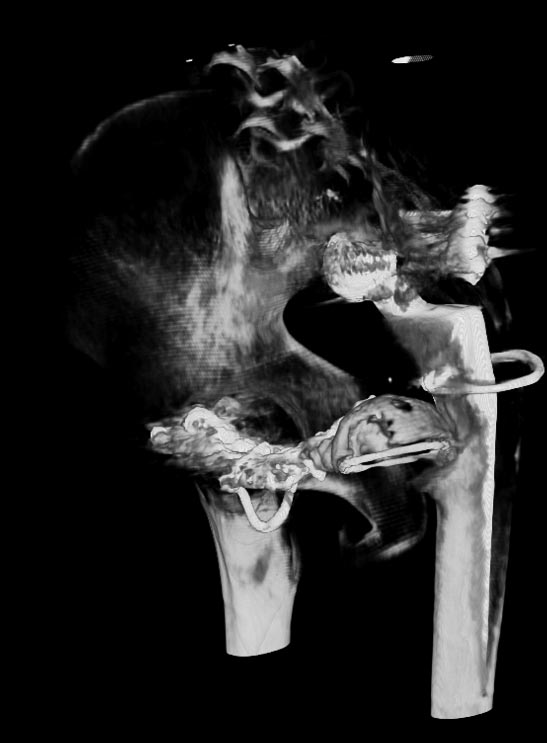

Мужчина 21 год, 2 года назад обнаружен эхиннокок костей таза, часть костей удалена сделано эндопротезирование и остеосинтез.Послеоперациооный период протекал гладко, через 6 месяцев упал, лечился консервативно, далее цепная реакция из проблем: гнойный остеомилит, свищи и лизис костей таза, на бак посеве эхинокок не обнаружен. Бедро не опорно, но больной предвигается на костылях. Картина маслом на рентгене и кт.об артродезировании думали, но диастаз большой, да и на фоне лизиса и остеопороза?????

Вложение не в текстовом формате было извлечено…

Имя     : ct2.jpg

Тип     : image/jpg

Размер  : 51229 байтов

Описание: отсутствует

Url     : http://weborto.net:8080/pipermail/ortho/attachments/20121127/db0e4c1e/attachment-0005.jpg